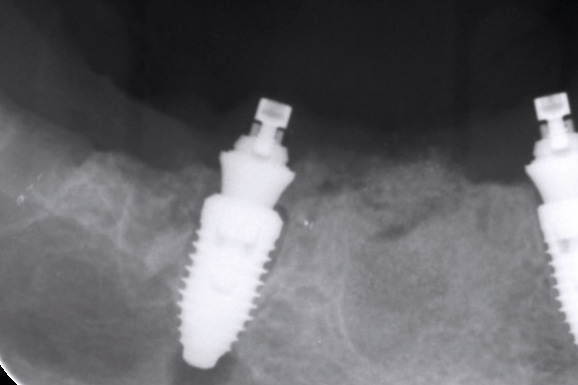

Multiple socket preservation in the mandibular with collacone® max – Dr. D. Jelušić